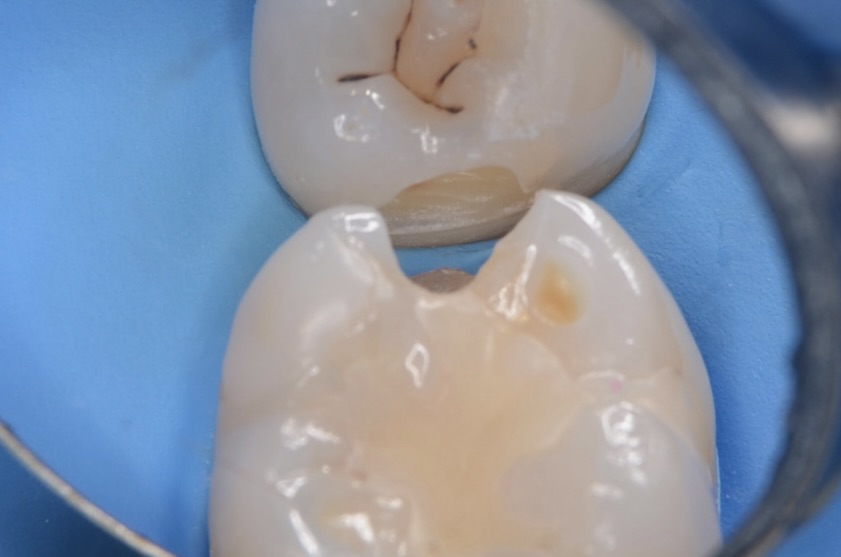

6番頬側の歯頸部

境目が茶色くなっている古いレジンがあります。 -

6番近心舌側の隣接面

茶色くなっている虫歯が見えます -